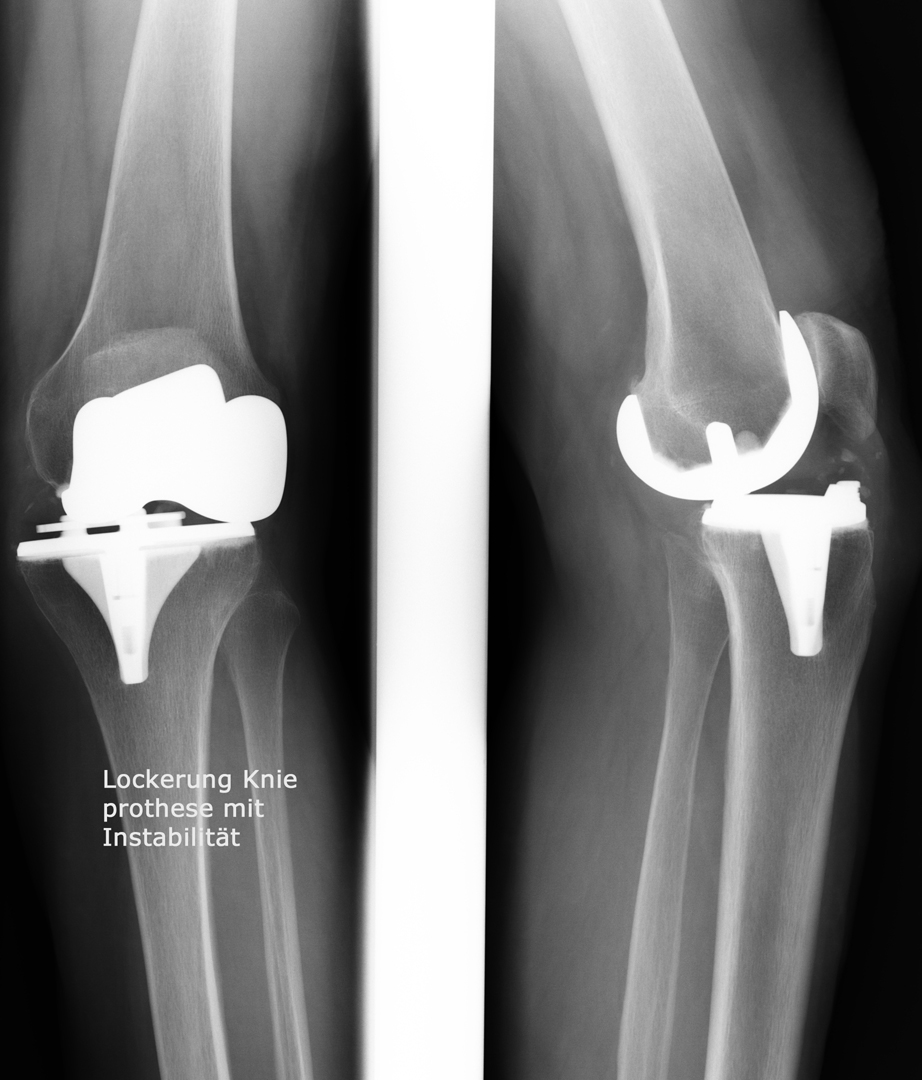

Knieprothese

Welcher Typ einer Knieprothese für die Behandlung der Kniegelenksarthrose verwendet wird hängt neben dem Patientenalter vorwiegend davon ab, welche Teile des Gelenks abgenützt sind. So können bei isolierten Abnützungen des inneren Gelenksteils sogenannte Schlittenprothesen ( linkes Bild) und bei Abnützungen des gesamten Gelenks Totalprothesen  (mittleres Bild) eingesetzt werden: In besonders schweren Fällen von Fehlstellung in Kombination mit fehlender oder unzureichender Bandstabilität werden auch immer wieder sogenannte achsegeführte oder gekoppelte Prothesenmodelle (rechtes Bild) eingesetzt.

Bild anklicken zum Vergrössern